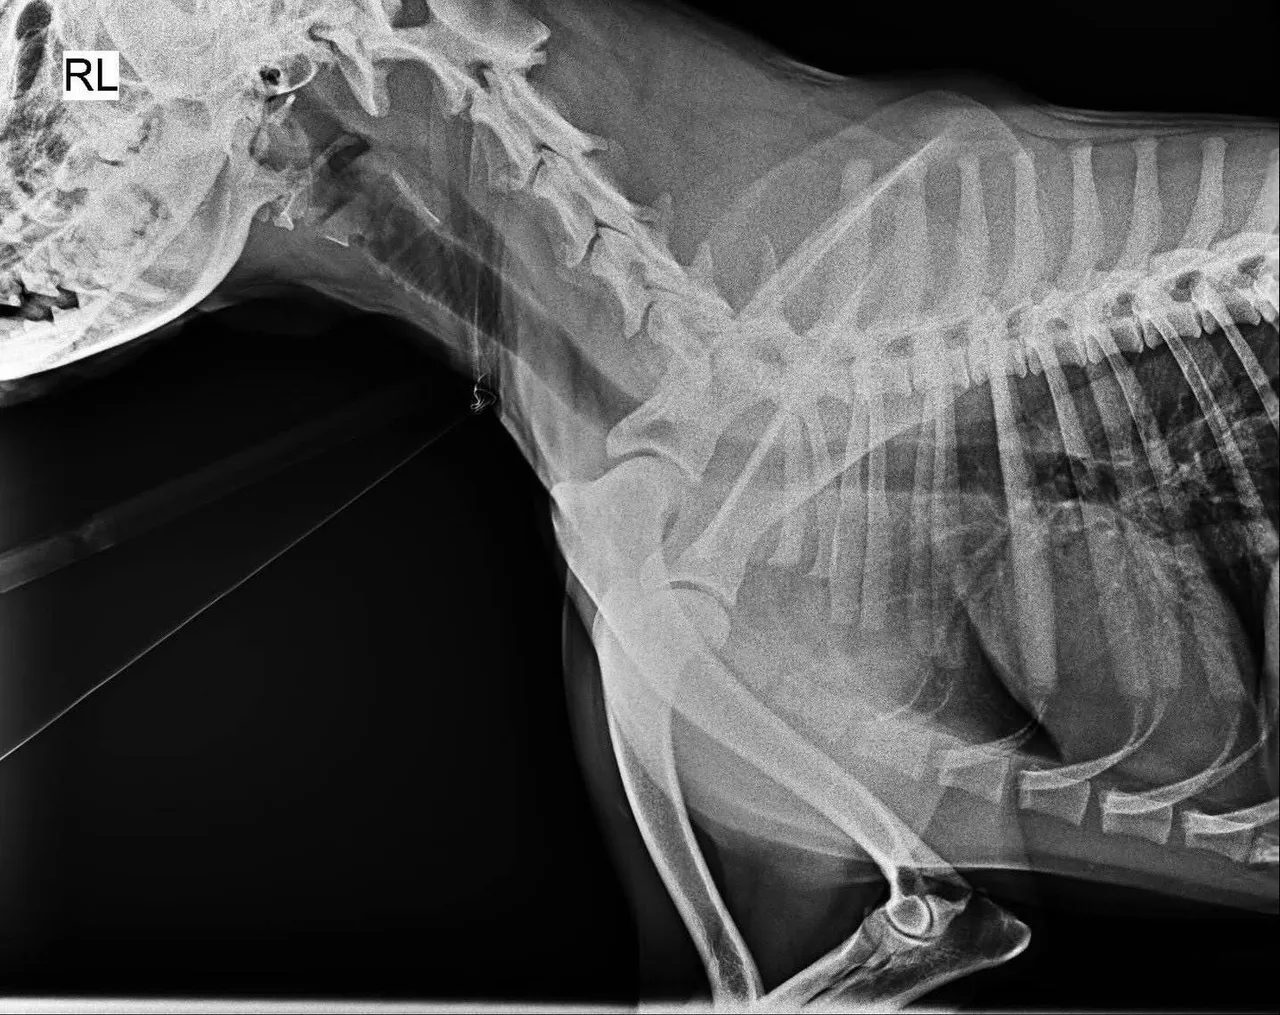

黑狗經X光檢查沒有骨折。江和樹提供